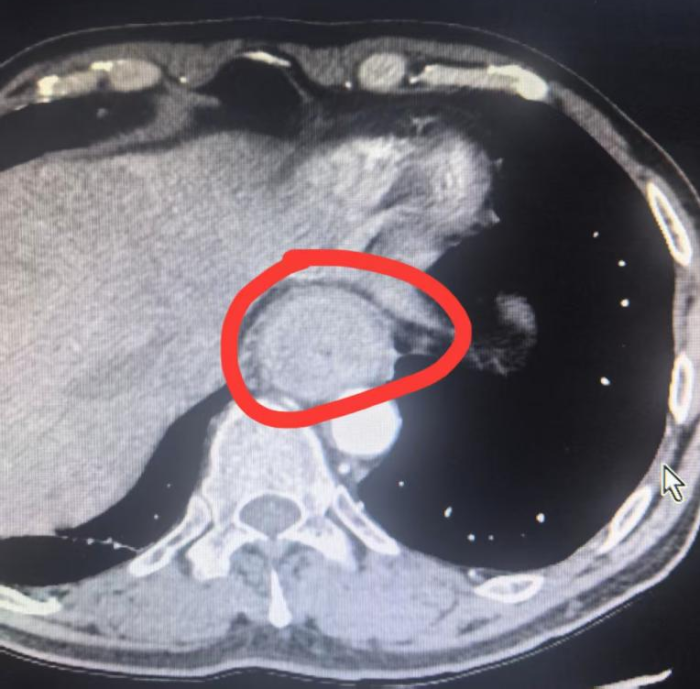

66岁的王大爷(化名)半年前感觉吃东西有些不顺畅,喉咙里像是有东西堵着,还有轻微的疼痛。刚开始没太在意,可这种梗阻感愈发严重,在当地医院做了胃镜检查。结果发现,距门齿 22—37cm 处可见食管不规则隆起,几乎把食管堵住了一半,此前的梗阻感就是因此而来。经过进一步的病理检查,王大爷被确诊为食管鳞状细胞癌。经亲戚介绍,王大爷来到了二附院找到吴云飞博士。

秦大叔(化名),今年63岁,于半年前出现进食哽咽症状,初期未予重视,后症状逐渐加重,进食米粉等食物时感到明显吞咽困难。随后,他在家人陪伴下前往当地医院就诊,经系统检查胃镜示食管距门齿约32-38cm环周见不规则隆起性肿物,粘膜质脆,触之易出血,仅能流质饮食。病理结果回示:食管鳞癌。由当地医院转到二附院治疗。

传统开胸手术风险高,吴云飞博士团队以全腔镜食管癌根治术——仅在胸腔开4个及腹部开5个约1厘米的小孔,在手术过程中胸心血管外科团队凭借丰富的经验和精湛的技术,小心地将各种器官、神经组织和血管一一分离预防各种手术并发症发生,然后精准地切除了胸段的食管肿瘤,并将腹部的胃进行游离和部分切除,制作成管状胃,完成了肿瘤切除、淋巴结清扫和消化道重建。